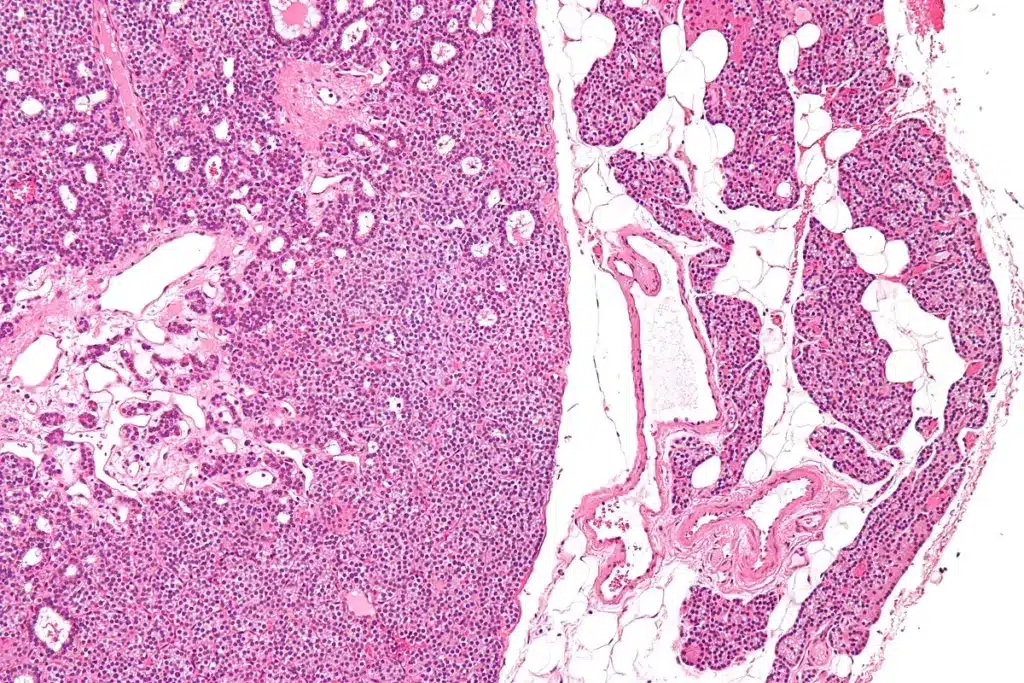

Primary Hyperparathyroidism

Primary hyperparathyroidism means too much parathyroid hormone (PTH) and calcium. It usually happens when one gland gets too active, often because of a tumor or too much growth. Symptoms include bone pain, kidney stones, and feeling very tired. A study shows it’s a common endocrine issue.